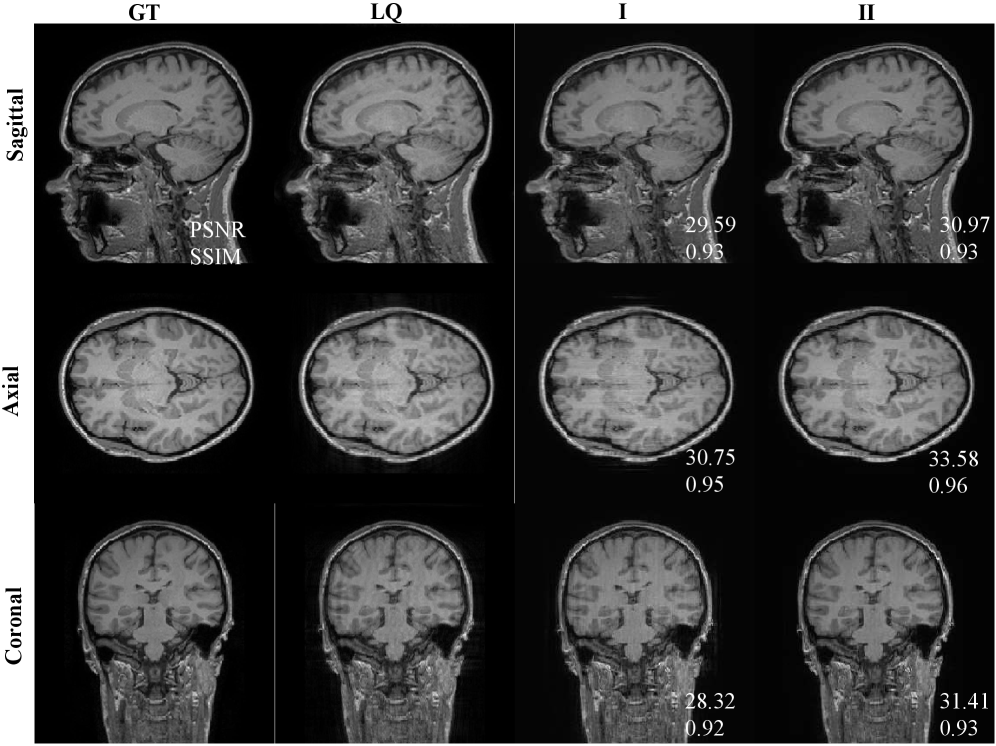

To verify the effectiveness of the algorithm in the real world, we deployed our algorithm and the comparison algorithms on real world data. The results are shown in Fig. 7. The 3DU-Net method benefits from paired learning and is effective at removing artifacts. However, current real-world data is not fully paired, causing the method to recover spurious structures that do not belong to the LQ images, which are most noticeable in the coronal plane. Furthermore, it exhibits significant over-smoothing compared to GT images. The BSA method is significantly more faithful to the LQ structure than 3DU-Net, but some errors in the results are also present, as shown by the red arrows. The SDE-MRI method can basically preserve the structure of the LQ images, but the regions indicated by pink arrows show insufficient artifact removal. This may be due to the inherent flaws of the method’s direct employment of weighted fusion. The PFAD method is better at removing artifacts than SDE-MRI, but significant structural errors and inter-slice discontinuities are observed, as indicated by the red arrows. This also reflects the imperfections of the two diffusion model-based methods in terms of structure preservation and artifact removal. In contrast, our method exhibits the capability to remove artifacts while preserving details in the LQ images even with unpaired data. This is due to the fact that our method does not learn the correspondence between the LQ images and the ground-truth images, but rather learns the degradation process from an image with motion artifacts to one without such artifacts. Furthermore, our pseudo-3D learning strategy avoids the inter-layer discontinuities that arise in 2D learning.

We randomly selected ROIs and evaluated the PSNR and SSIM metrics of several algorithms, as shown in Fig. 7. Because the 3DU-Net method completely learns the characteristics of the ground truth (GT) and fails to retain the key features of the LQ images, we believe that comparing its objective evaluation metrics against the GT is meaningless. Finally, our algorithm also exhibits significant advantages in terms of objective evaluation metrics.